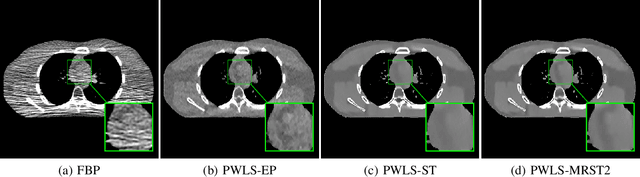

Signal models based on sparsity, low-rank and other properties have been exploited for image reconstruction from limited and corrupted data in medical imaging and other computational imaging applications. In particular, sparsifying transform models have shown promise in various applications, and offer numerous advantages such as efficiencies in sparse coding and learning. This work investigates pre-learning a multi-layer extension of the transform model for image reconstruction, wherein the transform domain or filtering residuals of the image are further sparsified over the layers. The residuals from multiple layers are jointly minimized during learning, and in the regularizer for reconstruction. The proposed block coordinate descent optimization algorithms involve highly efficient updates. Preliminary numerical experiments demonstrate the usefulness of a two-layer model over the previous related schemes for CT image reconstruction from low-dose measurements.